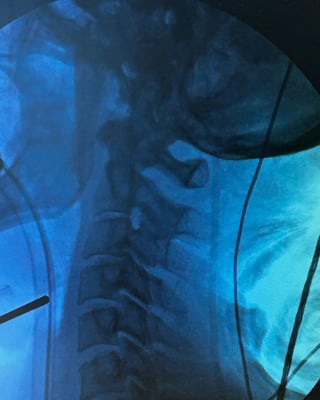

This month the IDE trial was intiatited with the first patient enrolled and surgery performed by Armen Khachatryan, MD at The Disc Replacement Center in South Jordan, UT. The surgery went well and the patient is doing great.

Group

Pre-Op

Post-Op

Image (from left to right): Eric Lange, Vice President, Reserch & Development, Dymicron; Armen Khachatryan, MD, Disc Replacement Center; Matt Allred, Nurse Practitioner, Disc Replacement Center.

Image: Pre-operative x-ray of disc degeneration at C3-C4 level in the cervical spine.

Image: Post-operative x-ray of Triadyme-C at C3-C4 level in the cervical spine.